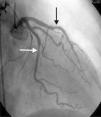

A 64-year-old white woman with a history of hypertension was admitted to hospital with new-onset chest pain consistent with angina. She had had multiple coronary angiograms (CA) four years previously for repeated episodes of typical chest pain and admissions. The CA showed non-obstructive coronary artery disease in the range of 40–50% in the left circumflex artery (LCx) which was confirmed to be non-obstructive by fractional flow reserve during the angiogram; no catheter-induced vasospasm occurred during the CA. Because of continued episodes of chest pain, she was taken off metoprolol and started on diltiazem 240mg once a day for possible vasospastic angina. She was then asymptomatic for the following four years, and also had a dobutamine stress echocardiogram, which was negative, about two months before the present admission for screening due to disease identified on her last CA. At this admission, she had new symmetrical anterolateral and inferior T inversion on the ECG consistent with ischemia; troponin levels were minimally elevated (0.3ng/ml). The patient had been seen by her primary care physician three days previously for a routine follow-up and was taken off diltiazem and started on nebivolol 10mg/day in addition to her medications of HCTZ 25mg and lisinopril 40mg/day, Lipitor 40mg, and enteric-coated aspirin 325mg/day for blood pressure (BP) control. In hospital she was started on nitro paste and intravenous (IV) heparin and her home medications continued. Because of continued chest pain in hospital and mildly elevated troponin I levels, she was scheduled for CA. She experienced chest pain at the beginning of the coronary angiogram, which initially revealed a 70% lesion and slow flow in the mid left anterior descending artery (LAD), a 90% lesion in the mid LCx and a 99% lesion in the ostium of the second obtuse marginal (OM2) (Figure 1, black arrow). The right coronary artery (RCA) had a distal 80–90% stenosis (Figure 2, black arrow). During preparation for percutaneous intervention in the LCx and OM2, intracoronary (IC) nitroglycerin was given for vessel sizing, after which there was resolution of the lesions in the LAD and decrease in the mid left LCx lesion to 50–60%, and resolution of the OM2 lesion, suggestive of significant reversible coronary artery spasm (Figures 3 and 4, white arrows). IC nitroglycerin was also administered in the RCA, in which lesion resolution was also seen. The coronary intervention was aborted, the patient's chest pain was resolved after IC nitroglycerin and she was started on IV nitroglycerin in the interim. Nebivolol was discontinued; diltiazem started in post-catheterization orders. She continued to have occasional episodes of chest pain for about 24hours after discontinuation of nebivolol. She was weaned from IV nitroglycerin the next day and started on oral isosorbide mononitrate. The following day the ECG changes resolved with no more episodes of chest pain; she was discharged home and was event-free in follow-up.